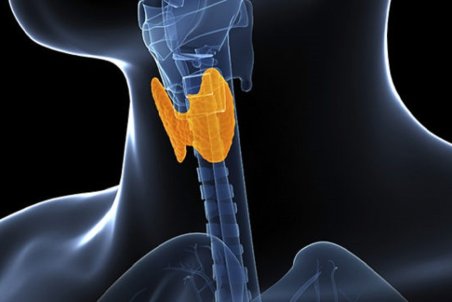

تیروئید یکی از بزرگترین غدد درونریز بدن است که به شکل یک پروانه مقابل حنجره و زیر گردن قرار گرفته است و هورمونهای بسیار مهمی ترشح میکند که بر عملکرد بدن مثل تنظیم دما، تپش قلب، کنترل سوخت و ساز، فعالیت مغزی و قدرت تفکر تاثیر دارد.